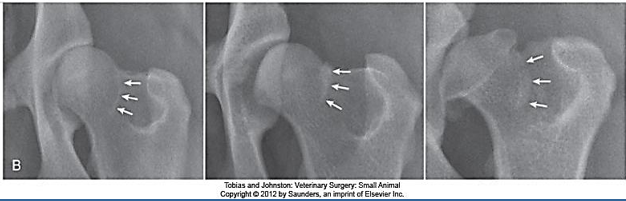

What are the typical radiographic findings of hip dysplasia?